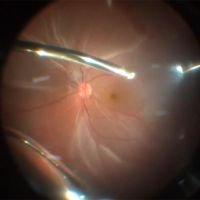

Retinal Detachment Surgery: Tips and Tricks Part 2

Mariano Iros, Tomás Castro Feijóo, Ahmed Sallam, Abdallah Ellabban, Frank Becquet, Juan Francois Le Rouic -